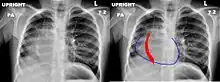

Le nom de ce syndrome vient de l'aspect angiographique du vaisseau anormal dont la forme, oblique en bas et en dedans, s'élargissant de haut en bas, évoque celle d'un cimeterre[3].